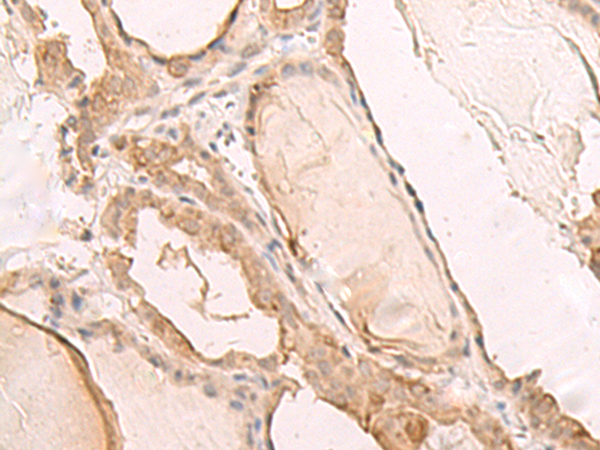

The image is immunohistochemistry of paraffin-embedded Human esophagus cancer tissue using P02793(PBXIP1 Antibody) at dilution 1/40. (Original magnification: ×200) |